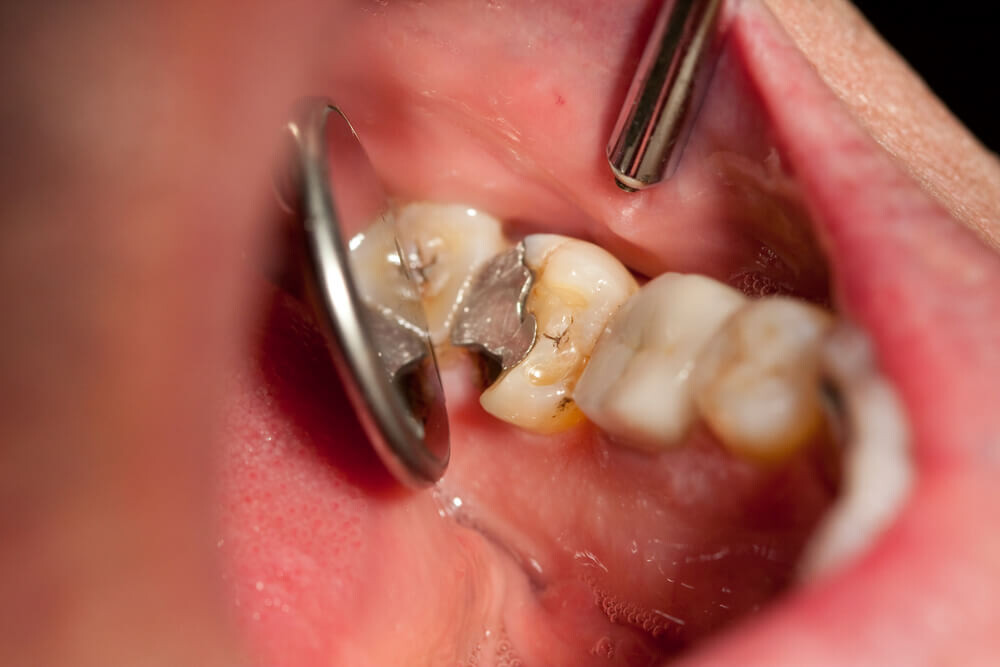

Tooth decay

As tooth decay progresses, it can reach the softer inner layers of the tooth, called dentin and pulp, resulting in sensitivity to hot, cold, or sweet foods and drinks and eventually leading to a toothache. If left untreated, tooth decay can result in an abscess, a painful infection at the root of the tooth that can cause severe pain and swelling. Adhering to your routine dental check-ups, practicing good oral hygiene, and eating a healthy diet can help prevent tooth decay and the resulting toothache.

A damaged filling

A damaged filling can cause toothache when the filling is no longer able to protect your tooth from external stimuli. When a filling is damaged, it can create an opening in the tooth, allowing bacteria to penetrate and cause an infection, leading to inflammation, swelling, and pain. Additionally, if you don’t replace the filling in time, it may cause your tooth to weaken or crack. A damaged filling may also cause sensitivity to hot and cold food and drinks.

Cavities are pretty common. As the National Institutes of Health points out, the only condition more common than a cavity is the common cold. If you've never experienced tooth decay, you might wonder, "What does a cavity feel like?" The answer depends on the stage of the cavity and what foods you eat. Some foods, such as sweets, might trigger the pain of a cavity more than others.

How Cavities Form

Signs of a Cavity

What does a cavity feel like? In the earliest stages, the answer might be nothing. There are no nerves in your tooth enamel, so when the decay is in that layer, you likely won't feel a thing. Once the decay has progressed enough to reach the softer tissues inside the tooth, where the dentin and nerves are, you might notice signs of a cavity. Your teeth might feel sensitive and you could feel some pain, especially after eating sweets, hot foods or cold foods. The pain can be fairly mild or sharp and intense. Some people with cavities also feel pain when biting down.

Depending on the size of the cavity, you may be able to see evidence of it in your mouth. Cavities sometimes create visible holes in the teeth. They can also create stains that are black, brown or white on the surface of the tooth.

What should you do if you think you have a cavity? The first step is to see your dentist. Although cavities can be reversed in the early stages, by the time you are feeling discomfort or pain, only a dentist can treat them. An x-ray will be taken to determine how the cavity has progressed into the tooth. Depending on how severe the cavity is, you might need a filling to fix it. If the decay is very severe, the dentist might replace the tooth with a crown or perform a root canal.